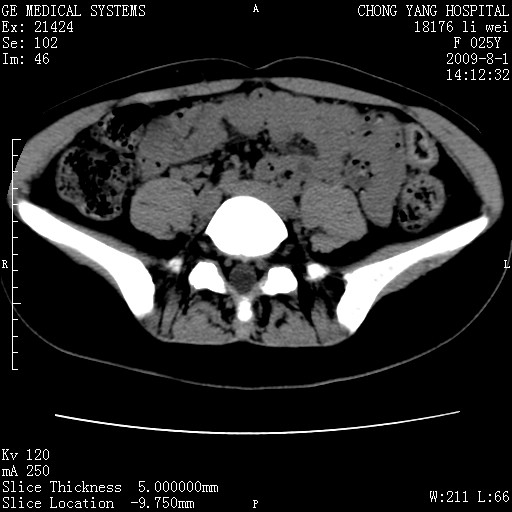

以下是引用pujunzhi在2009-8-1 20:23:00的发言:[br]胸椎旁及背部肌间良性病变,范围广,边界清,沿肌间生长,考虑淋巴管瘤、血管瘤,建议增强扫描。

以下是引用拾荒者在2009-12-30 21:45:00的发言:[br]ct21383:神经纤维瘤病( nf) [br] [br] 神经纤维瘤病。四肢都有,影响美观,四肢上的手术了。[br] [br] [br]谢谢!